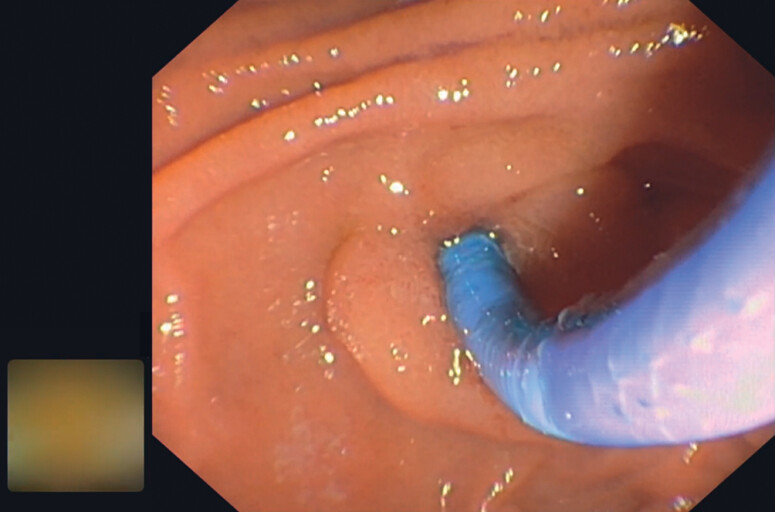

Informed consent was obtained from all patients. All patients received a single dose of prophylactic intravenous antibiotics (third-generation cephalosporin) prior to cholangioscopy. All procedures were performed under moderate sedation with midazolam, propofol, and fentanyl in prone position. If procedure time was expected to be more than 1 hour or at anesthetist discretion, the procedure was performed under general anesthesia with endotracheal intubation. Antibiotic prophylaxis was administered in all patients at the time of the procedure. A therapeutic duodenoscope with a 4.2-mm channel (TJF Q180V, Olympus, Tokyo, Japan) was used for endoscopic retrograde cholangiopancreatography (ERCP). After CBD cannulation, a cholangiogram was obtained and the size of the lower CBD (1 cm proximal to papillary opening) and stone size were measured ( Fig. 1 ). Sphincterotomy size (Ultratome XL, Boston Scientific, Massachusetts, United States) and further balloon dilatation (Hurricane or CRE, Boston Scientific, Massachusetts, United States), was left to endoscopist discretion. If balloon dilatation was performed, balloon size never exceeded the lower extraduodenal CBD diameter, which was measured 1 cm proximal to the papillary orifice. Sphincterotomy was not extended in patients with previous sphincterotomy. Cholangioscopy was performed with the Spyglass DS system (Spyscope DS, digital controller, access and delivery catheter, Boston Scientific, Massachusetts, United States), equipped with an irrigation and aspiration system. The cholangioscope was introduced through the 4.2-mm working channel of the duodenoscope using a free-hand technique ( Fig. 2 ). In case of sharp angulation in the lower bile duct, the cholangioscope was introduced in the CBD over the wire (0.025, Visiglide, Olympus, Tokyo, Japan). We chose 0.025-inch wire because it has similar strength to a 0.035-inch wire and we did not encounter any difficulty with the 0.025-inch wire.

Electrohydraulic lithotripsy (EHL) was performed using a 1.9F bipolar electrode probe (Nortech, Elgin, Illinois, United States) with Northgate SD – 100 generator (Northgate Research Inc. Arlington Heights, Illinois, United States) ( Fig. 3 ). The energy setting was 75 volts and increased gradually to a maximum of 90 volts. Energy was applied in bursts of variable duration, at a frequency of five to six shocks per second.